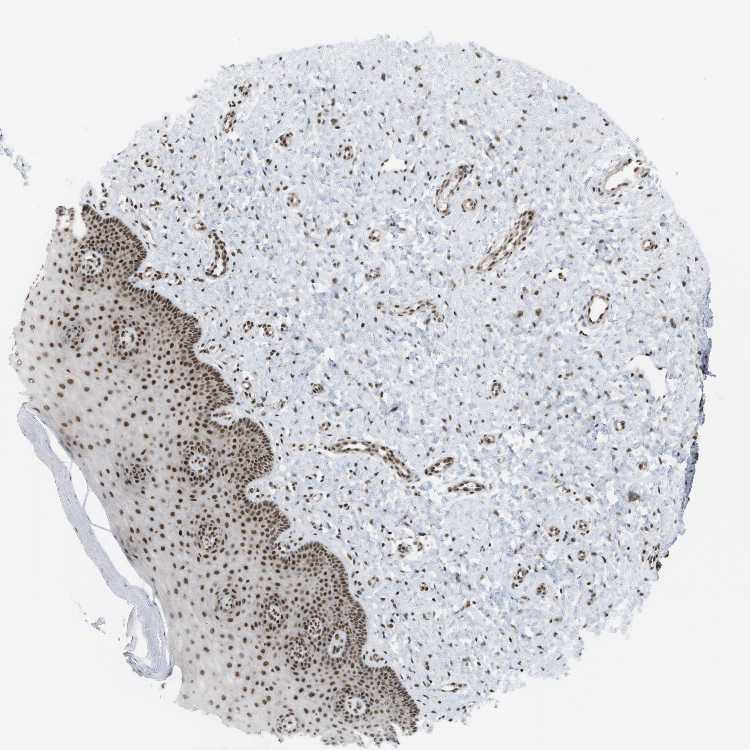

CERVIX - Antibody stainingi

Antibody staining in the annotated cell types in the current human tissue is reported as not detected, low, medium, or high, based on conventional immunohistochemistry profiling in selected tissues. This score is based on the combination of the staining intensity and fraction of stained cells.

Each image is clickable and will lead to virtual microscopy that enables deeper exploration of all samples and also displays staining intensity scores, fraction scores and subcellular localization as well as patient and tissue information for each sample.

Antibody HPA017224

Glandular cells High

Squamous epithelial cells High